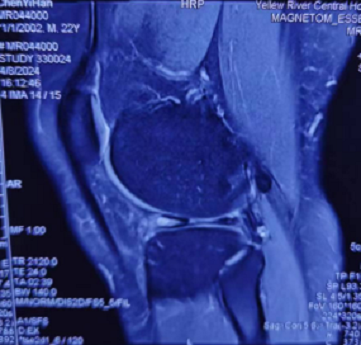

由于患者年轻,活动量大,且新鲜损伤,主任医师闫鹏为陈某实施了膝关节镜下半月板缝合修复术,手术仅需要做2个5mm小切口,术中直视下证实了患者半月板撕裂。手术非常顺利,最大程度保留了患者的半月板,且切口很小,不影响美观。

▲ 术中镜下所见